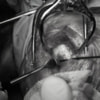

関節穿刺を行い、好中球はなく、少数のマクロファージや滑膜細胞が認められるました。膝蓋骨脱臼および前十字靭帯断裂による退行性の関節炎を疑い、関節鏡検査を実施いたしました。関節鏡検査では、重度の滑膜炎および前十字靭帯の完全断裂が認められました。内外側とも半月板に損傷は認められませんでした。

■ 外科的治療法

断裂前十字靭帯の除去を行いました。外側方向からのテンションが著しく、外側広筋と膝関節外側支帯の解放を行いました。膝関節伸展機構の著しいアライメント異常が認められたため、脛骨粗面転移術を実施しました。

写真の膝関節の垂直線を綿棒の木柄が表しており、遠位の脛骨粗面との位置関係が平行ではありません。

転移側の骨床は犬種特有の変形した表面であったため、転移後の骨片の圧着状態が改善するように変形表面をラウンドバーにて切削しました。滑車溝の著しい低形成が認められたため、滑車溝形成術を実施いたしました。

切断された関節包の縫縮を行いました。前十字靭帯断裂後の不安定性と内旋を解消するために、人工靭帯(fiber wire)によるラテラルスーチャー法を併用し安定化を図りました。

術後、整形外科学的検査における脛骨圧迫テストや前方引き出し兆候は認められませんでした。